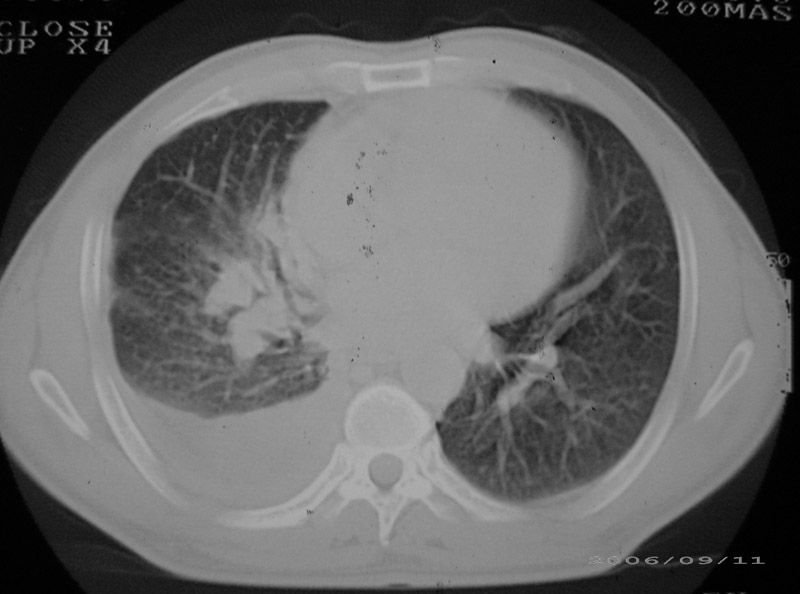

以下是引用守望可可西里在2006-9-11 15:29:00的发言:[br][br] ct平扫表现:右侧胸膜腔缩小,积液,胸膜增厚且不均匀、不规则,以纵隔胸膜增厚为主,边缘呈锯齿状,并见附壁内突之结节状肿块影。右肺含气量减少,纹理聚集,右肺门中下部见数个肿大的淋巴结。纵隔无移位,内未见明显肿大淋巴结,双侧主支气管以及各叶、段支气管比较通畅。。[br] 考虑:右侧胸膜恶性间皮瘤,伴肺门淋巴结转移。